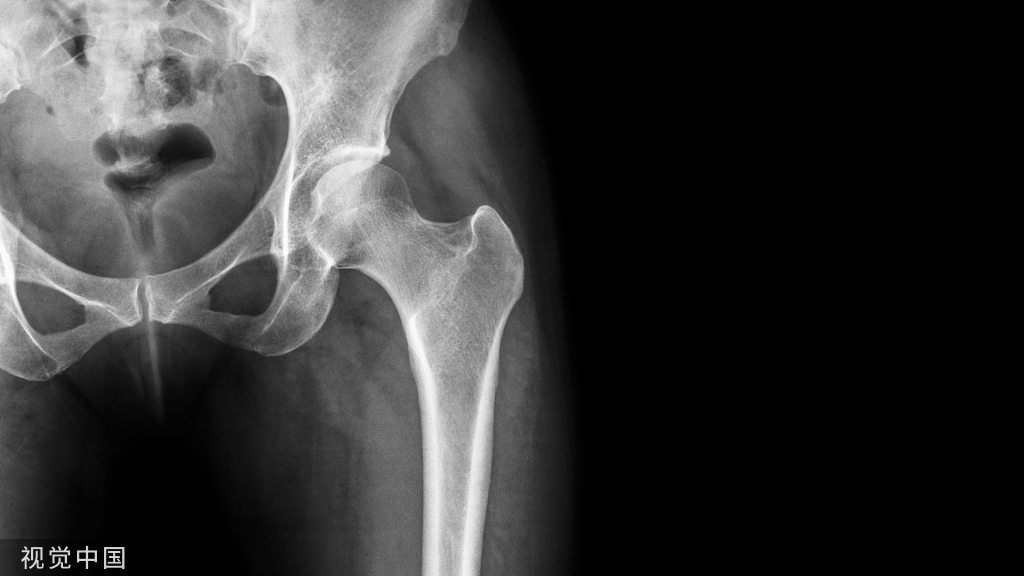

髋部骨折

一、髋部骨折患者术前翻身方法:

两人翻身法:1、操作者分别站在病人患侧的床边,先将病人的双手放于胸前,让病人屈曲健侧膝关节,操作者一人双手分别放至病人的肩和腰部,另一人将双手分别放至病人患肢的膝部小腿维持轴线牵引,先让病人健侧下肢配合用力,同时将身体抬起移向患侧床沿。

2、让病人稍屈曲健侧膝关节,在两膝间放置2-3个枕头,高度以病人双侧的髂前上棘之间的距离再加上5厘米,操作者一人双手分别放至病人的肩和腰部,另一人维持患肢轴向牵引力,两人同时将病人翻向健侧,将患肢置于两膝间的枕头上,保持患肢呈外展15度、髋膝伸直位牵引,然后在病人的背部垫软枕,胸前放一软枕放置上肢。